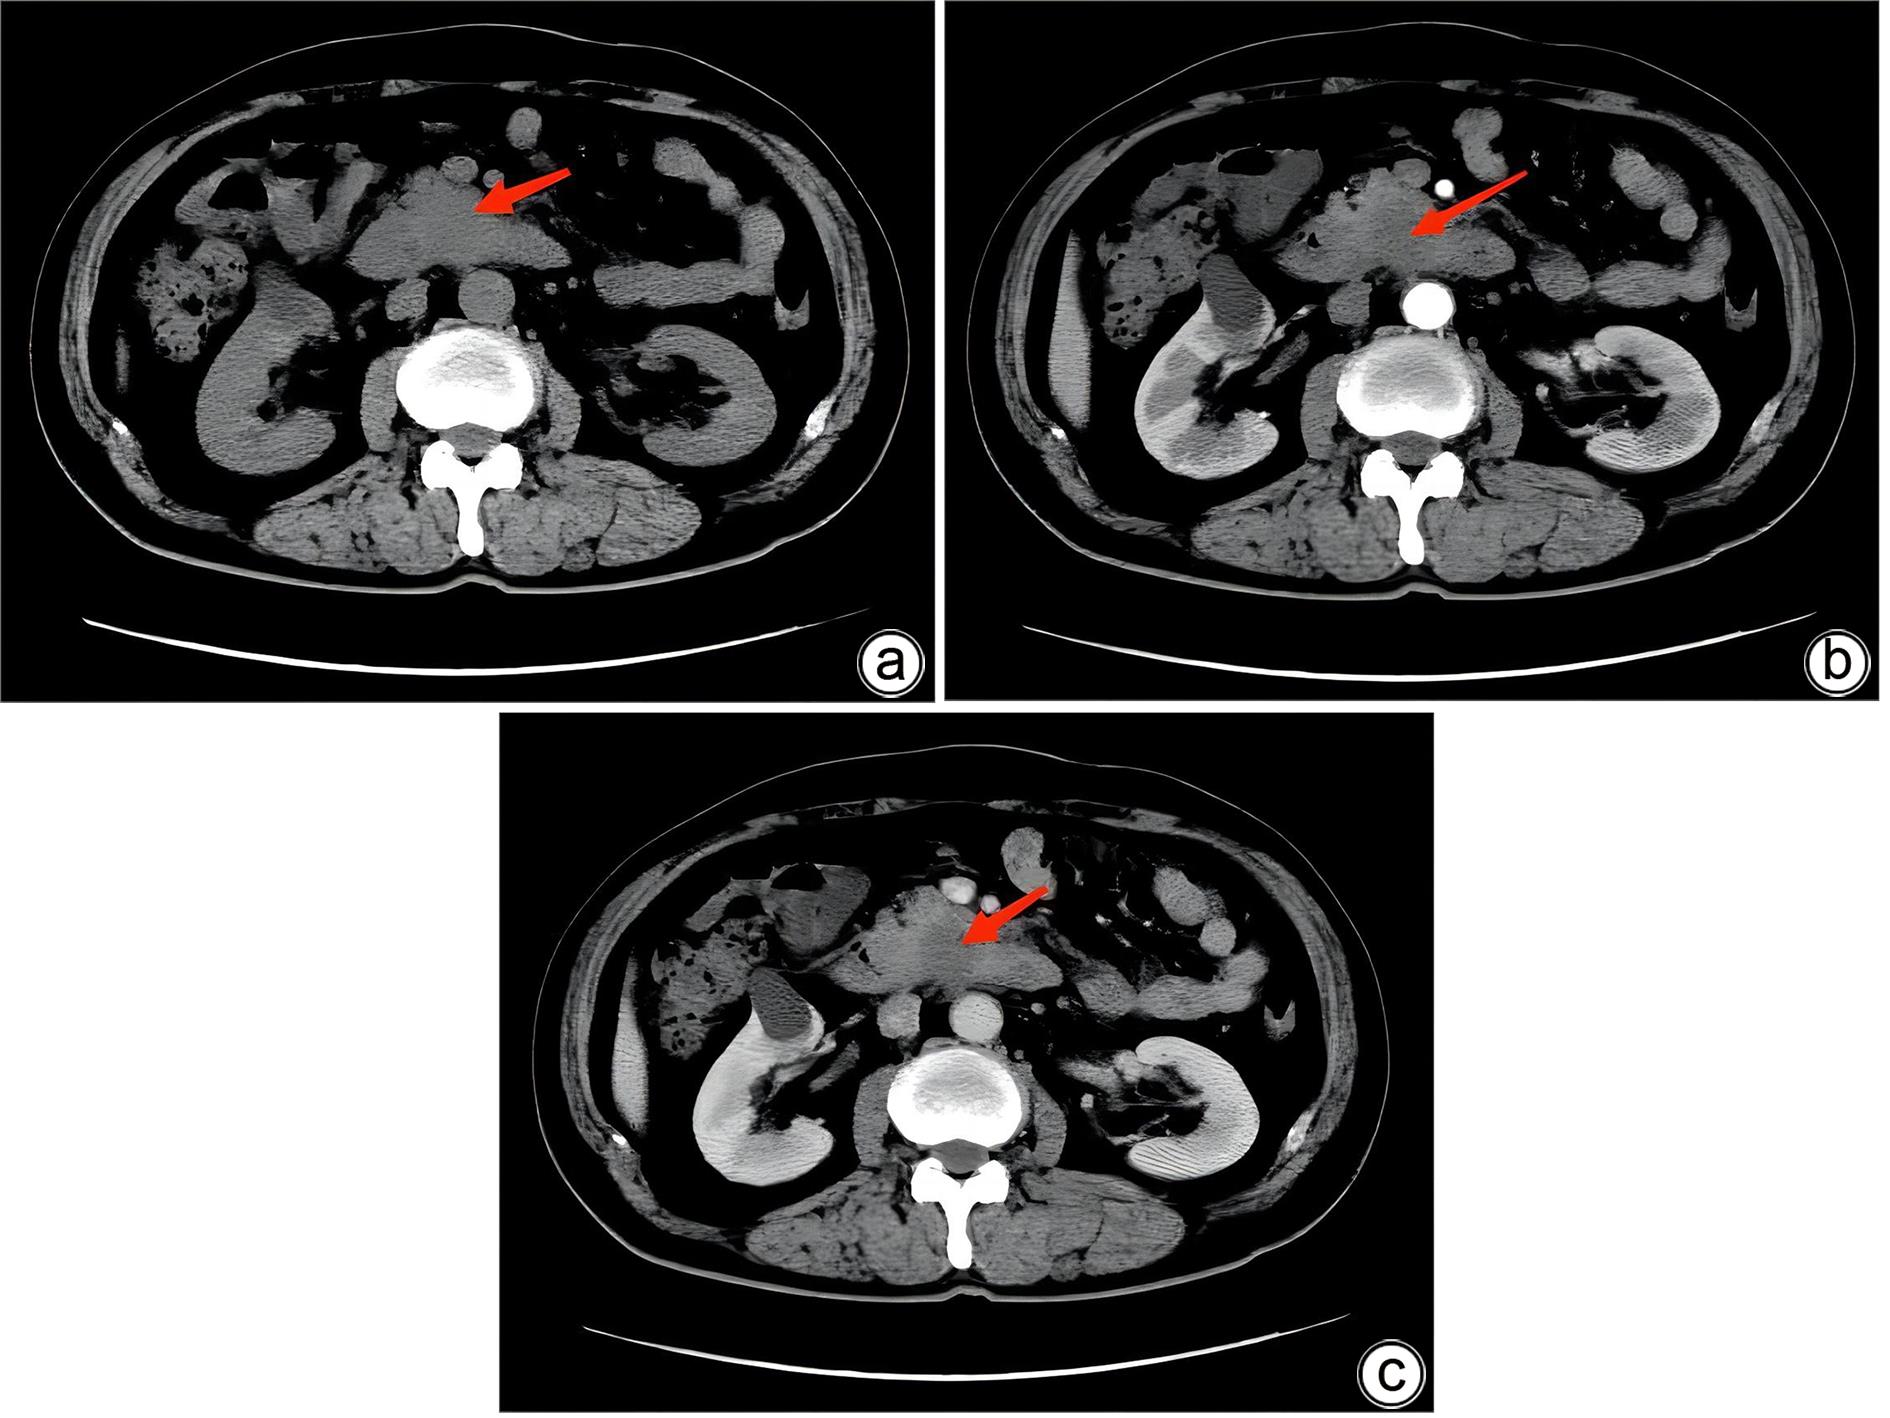

胰腺内副脾误诊2例报告

2024, 40(2): 365-368. DOI: 10.12449/JCH240223

摘要(1364) HTML (331) PDF (1188KB)(157)

摘要:

副脾是指正常脾脏以外存在的,与主脾结构相似,有一定功能的脾脏组织,其中完全被胰腺包裹的胰腺内副脾(IPAS)发生率仅为2%,因其临床症状不典型,影像学特征与胰腺神经内分泌肿瘤、胰腺实性假乳头状瘤以及其他胰腺占位性病变较为相似,临床上容易误诊。本文报道了2例分别被误诊为胰腺神经内分泌肿瘤和胰腺实性假乳头状瘤的IPAS患者,并分析误诊原因,总结诊疗经验,以期提升临床对IPAS明确鉴别诊断的认识。